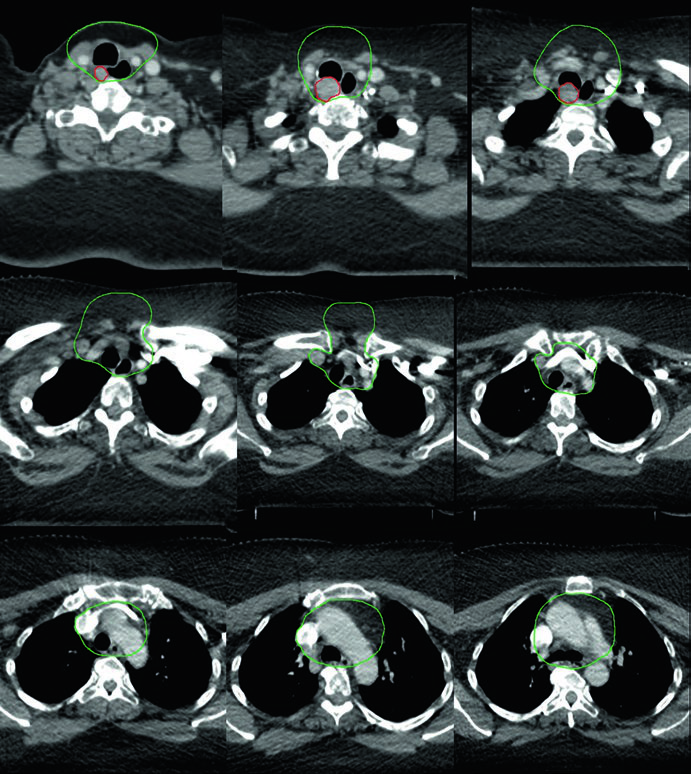

Caso 1 — Carcinoma papilar metastático (Fig. 9.1): Homem de 58 anos com carcinoma papilar metastático de tireoide, submetido a múltiplas ressecções prévias, que se apresentou com recorrência local irressecável e múltiplos linfonodos mediastinais. Recebeu quimiorradioterapia definitiva para prevenir progressão local. O CTV70 Gy (vermelho) abrange a recorrência local e linfonodos mediastinais envolvidos, enquanto o CTV60 Gy (verde) cobre as regiões subclínicas de risco. Este caso exemplifica o cenário de doença recorrente que esgotou as opções cirúrgicas — a radioterapia com dose definitiva é a melhor alternativa para controle local.

Caso 2 — Carcinoma anaplásico irressecável (Fig. 9.2): Mulher de 73 anos com carcinoma anaplásico de tireoide invadindo laringe, traqueia e esôfago. Recebeu quimiorradioterapia definitiva com doxorrubicina concomitante. O CTV70 Gy (vermelho) engloba toda a doença volumosa, e o CTV60 Gy (verde) abrange o risco subclínico. Detalhe importante: o manúbrio, que normalmente não é incluído no volume de risco, foi englobado neste caso específico por conta da doença volumosa anterior agressiva no pescoço. Essa decisão é atípica e deve ser individualizada — não se trata de protocolo, mas de resposta a uma apresentação clínica particular.

Caso 4 — Recorrência multifocal de variante de células altas (Fig. 9.4): Mulher de 61 anos com variante de células altas do carcinoma papilar, submetida a três cirurgias prévias, que se apresentou com recorrência multifocal. Foi tratada com quimiorradioterapia definitiva. O GTV70 Gy (vermelho) demarca cada foco de recorrência, e o CTV60 Gy (verde) cobre o pescoço subclínico em risco. A variante de células altas é reconhecidamente mais agressiva que a variante papilar clássica, com maior propensão a recorrência e comportamento biologicamente mais adverso.

Caso 5 — Câncer pouco diferenciado, fenótipo folicular (Fig. 9.5): Mulher de 69 anos com câncer de tireoide pouco diferenciado de fenótipo folicular, aderido a traqueia e esôfago, submetida a ressecção e iodo radioativo, que recorreu com massa paratraqueal direita invadindo a traqueia. Após nova ressecção e esvaziamento cervical, recebeu quimiorradiação adjuvante. O CTV60 Gy (verde) cobre o compartimento central e o mediastino superior. O tratamento do pescoço lateral foi omitido, dada a alta probabilidade de recorrência no compartimento central — a dose e o risco foram priorizados onde o benefício clínico era máximo.